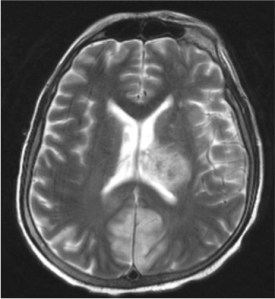

A middle-aged man presented with acute lymphoblastic leukemia (initial white cell count of 150,000 per cubic millimetre of blood – mostly blasts). After completing a course of hyper-CVAD, he developed persistent febrile neutropenia that was unresponsive to antibiotics. On the 6th day of fever, CT thorax was performed which was normal. On the 8th day of fever, he suddenly became drowsy and an MRI brain was performed. Sample images are shown below.

He was brought down to the intensive care unit (ICU) in view of his drowsiness and the brain lesions, and a skin lesion appeared over his face the following day.

These constellation of features suggest an opportunistic invasive fungal disease, and its rapidity of development is consistent with mucormycosis – a fungal infection caused by the Mucorales group of fungi. The following figure is a microscopic image of the fungus (Rhizopus spp.) cultured from this patient’s sinuses and skin lesion.